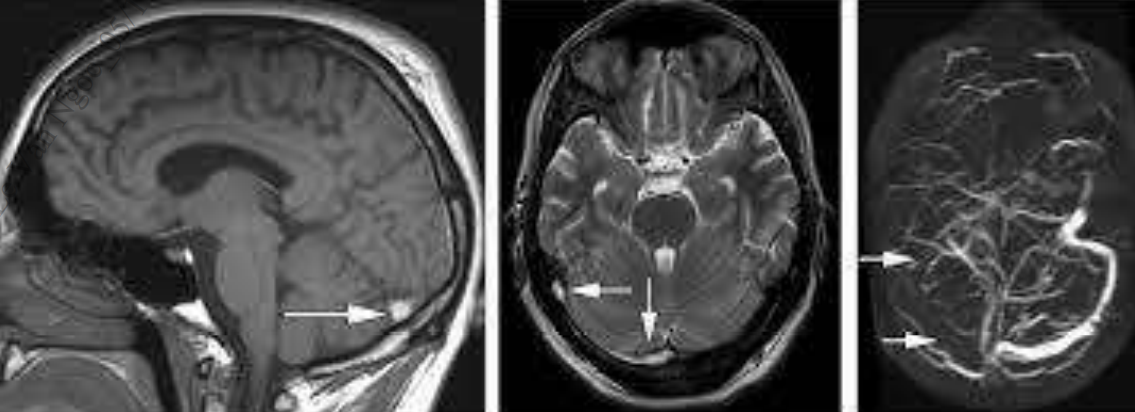

MRI sử dụng hình ảnh T2* kết hợp với chụp tĩnh mạch (MRV) là phương pháp hình ảnh nhạy nhất để chẩn đoán huyết khối tĩnh mạch não. Các đặc điểm của tín hiệu MRI phụ thuộc vào tuổi của huyết khối:

• Trong năm ngày đầu tiên, các xoang bị tắc nghẽn xuất hiện đồng tín hiệu trên T1, giảm tín hiệu trên T2.

• Sau năm ngày, huyết khối tĩnh mạch trở nên rõ ràng hơn: tăng tín hiệu trên T1 và T2.

• Các tổn thương nhu mô não thứ phát bao gồm phù não hoặc nhồi máu tĩnh mạch là giảm tín hiệu trên T1 và tăng trên T2.

• Chụp cộng hưởng từ tĩnh mạch(MRV): rất hữu ích để thấy tắc xoang tĩnh mạch não: có hình ảnh mất tín hiệu dòng chảy trong các xoang tĩnh mạch bị tắc do huyết khối.

Hình 3: Hình tăng tín hiệu trên T1 và T2; CHT tĩnh mạch có hình ảnh mất tín hiệu dòng chảy trong xoang tĩnh mạch ngang bên phải.